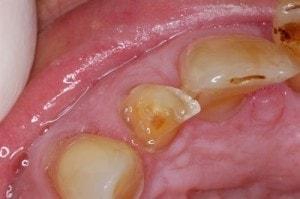

Caries in incisor teeth

Decay in teeth #'s 7, 8, and 10

Immediate objective is to manage the more serious cavities, and then address periodontal issues.